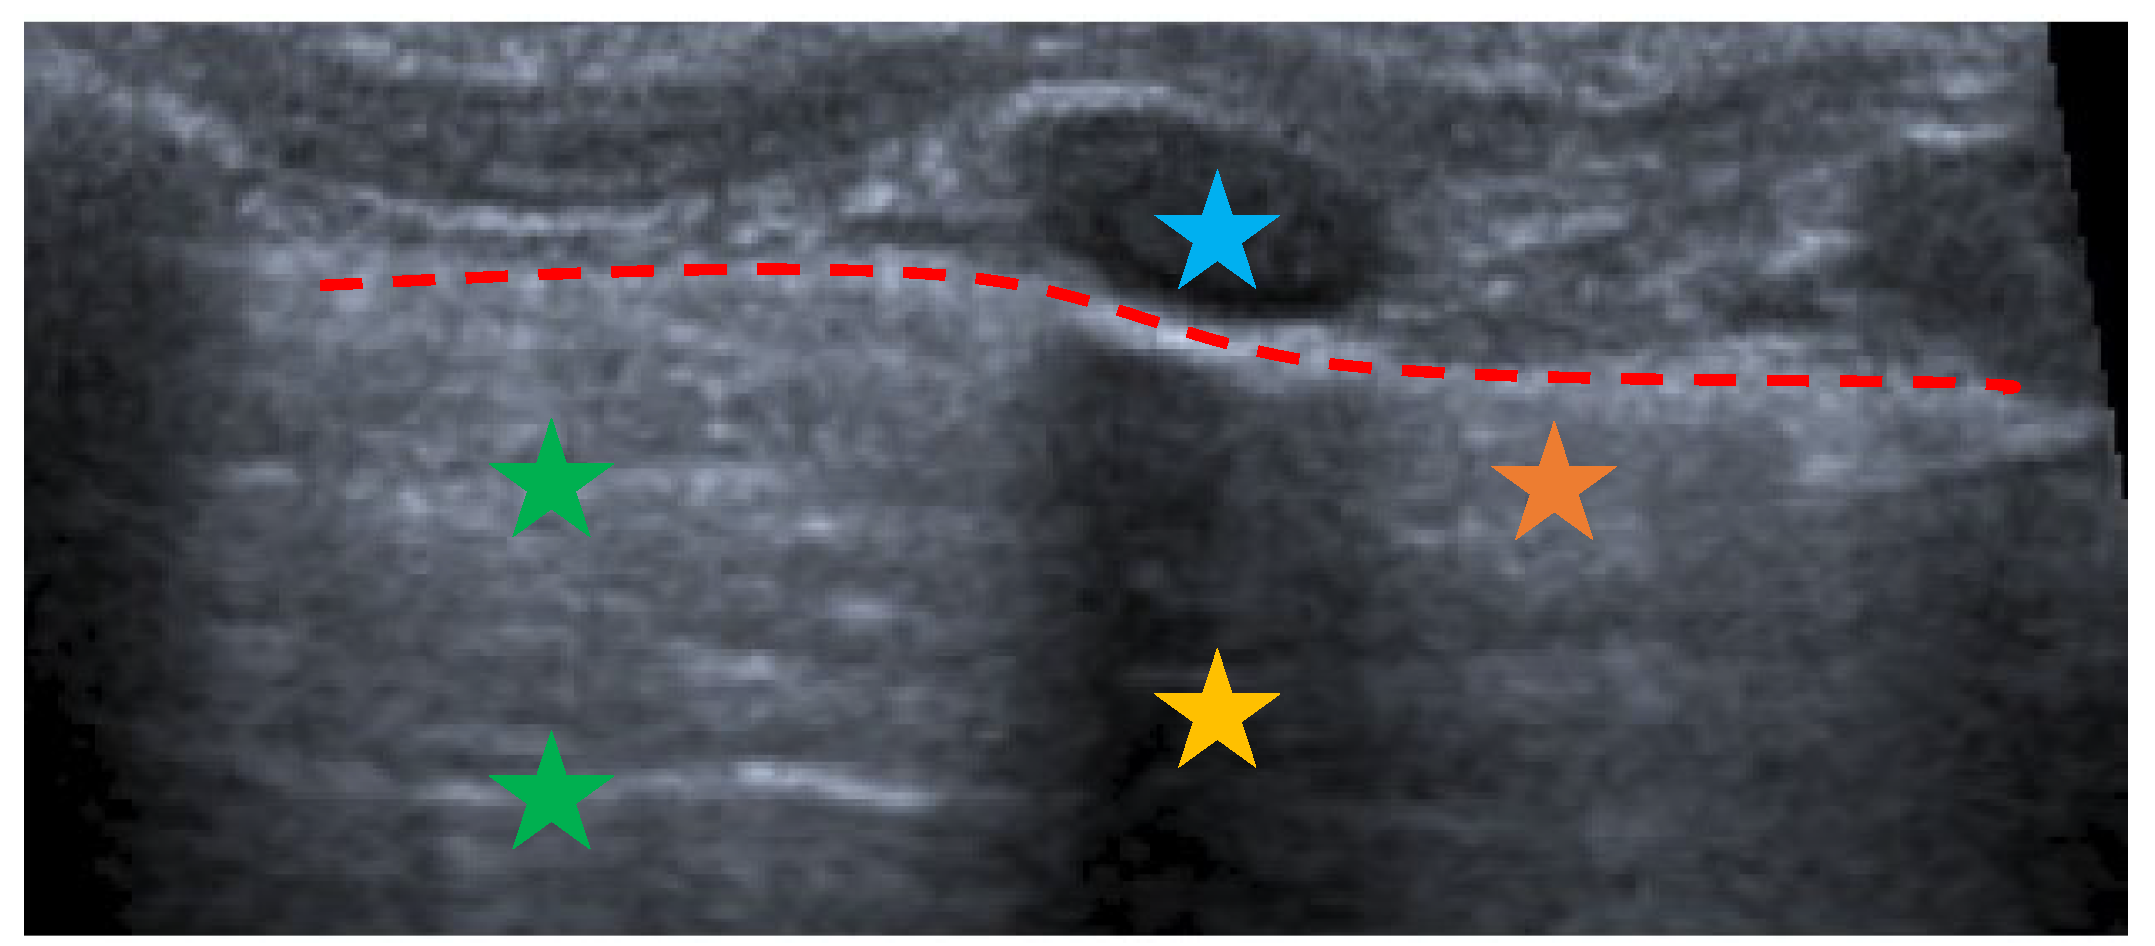

3. Lung Ultrasound: Where Do We Start

- The presence of A-lines.

- The presence of B-lines, their characteristics (short or long, spared or confluent) and their location (peri-lesional, monolateral/bilateral).

- The main lesion (consolidation): size, whether it is single or multiple, location (monolateral or bilateral). The presence of small subpleural consolidations (<1 cm).

- The presence of a bronchogram and its characteristics (air or fluid), morphology (branched or dot-like), dynamics during breathing (poorly or clearly dynamic); vascular pattern, presence of lung point and pulmonary pulse.

- The presence of lung sliding (M-mode).

- The presence and type of pleural effusion.